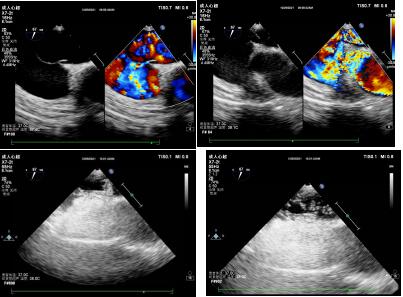

患者2

据了解,部分患者行经胸超声心动图检查时,因自身条件、检查方式等客观原因,导致较小的心脏疾病容易漏诊。然而,经食管超声心动图检查作为经胸超声心动图的补充检查,可以更加直观、清晰地观察心脏内部结构,在先天性心脏病、瓣膜性心脏病、心脏肿瘤、血栓等疾病诊断中具有重要意义。尤其是在持续性头痛、不明原因脑卒中、动脉栓塞等患者中,可能会存在卵圆孔未闭这一心脏疾病。经食管超声心动图联合由右心声学造影检查可清楚显示卵圆孔的结构、大小、形态,分别在患者静息状态及Valsava动作下,通过观察房间隔卵圆孔处血流信号、造影剂微气泡的分流情况,准确诊断卵圆孔未闭,从而指导临床医生及时治疗,有效预防患者潜在脑血管意外事件的发生。